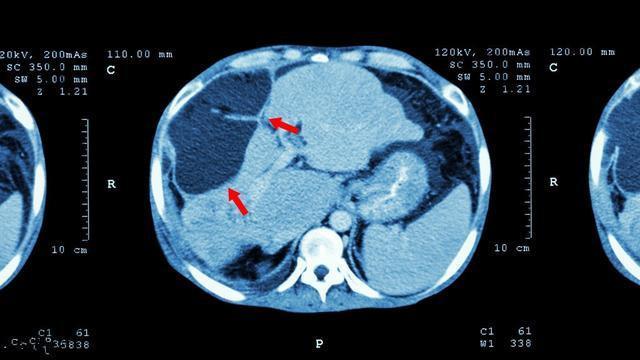

近日,张大爷频繁出现肝部疼痛的症状,而且一天比一天难以忍受,在朋友的劝说下他来到医院进行检查,没想到医生拿到检查报告后告诉他,由于多年的肝炎久治不愈病症已经转化为肝癌了。这让本以为自己病情已经控制的张大爷后悔莫及。

据了解,肝癌的发病率在所以癌症中排在第一位,我国肝癌每年发病人数约有35万人,占到全球肝癌人数的一半左右。专家表示,从肝炎到肝癌其实也只需要三个步骤:乙型肝炎患者有1/3的概率会发展成肝硬化,肝硬化中也有1/3会恶变为肝癌。但是肝癌并非“不治之症”,部分肝癌已经能够临床治愈,关键是早发现、早期治疗。